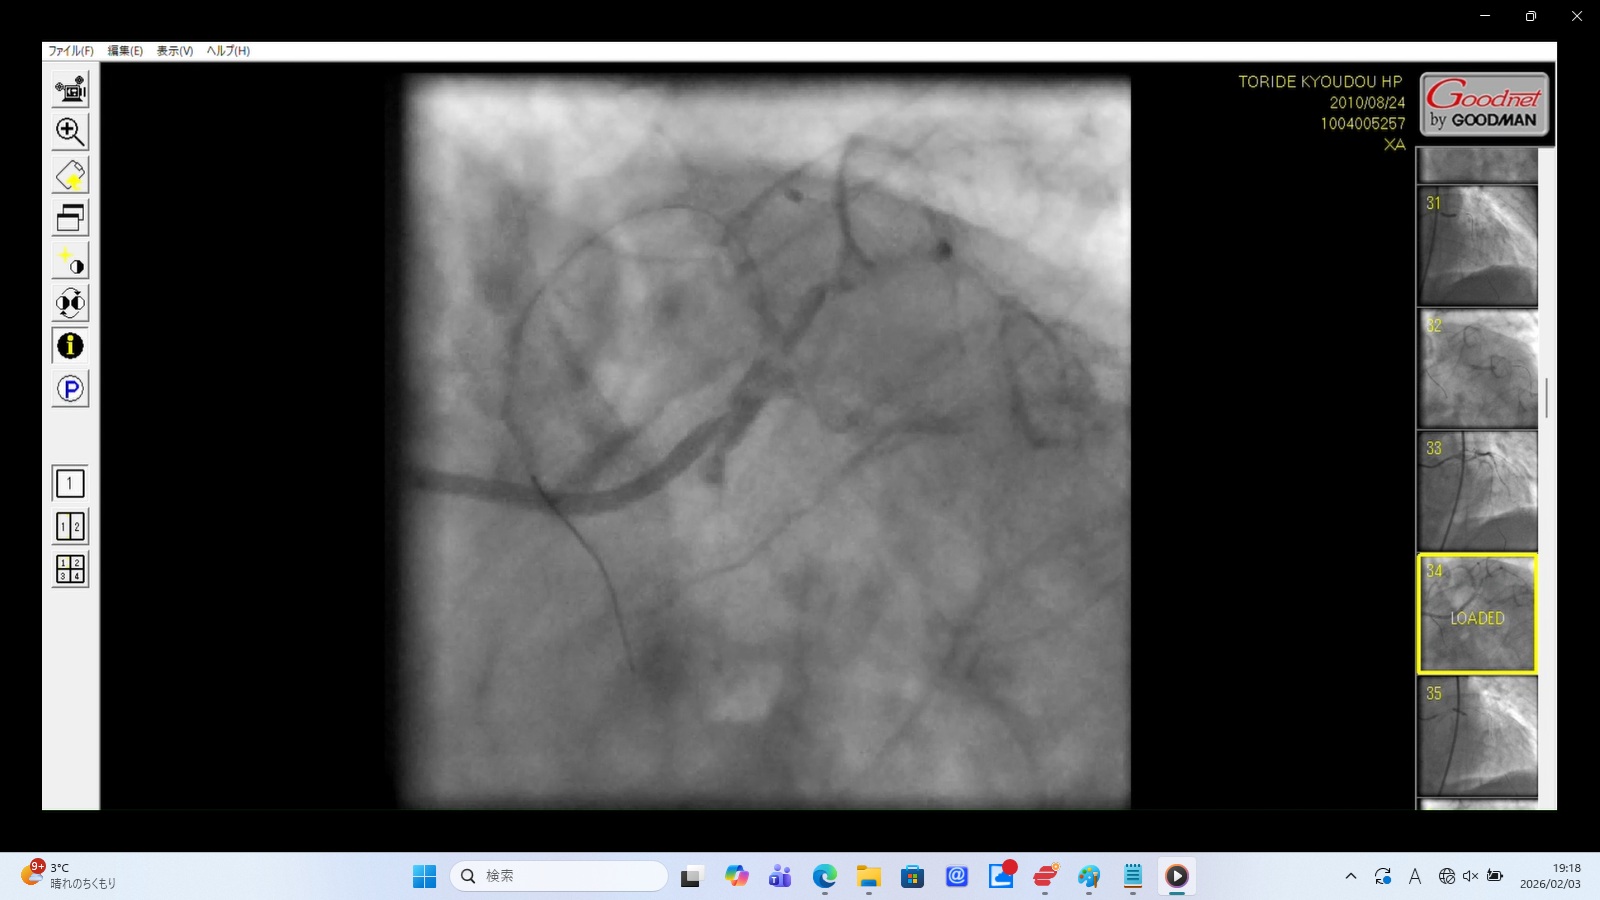

Finding: Presence of a false lumen within the Left Main Trunk (LMT) and direct leakage from the LMT into the exterior.

Interpretation: This confirms severe structural failure of the coronary artery. The LMT has been functionally destroyed, leading to both internal dissection and external hemorrhage.